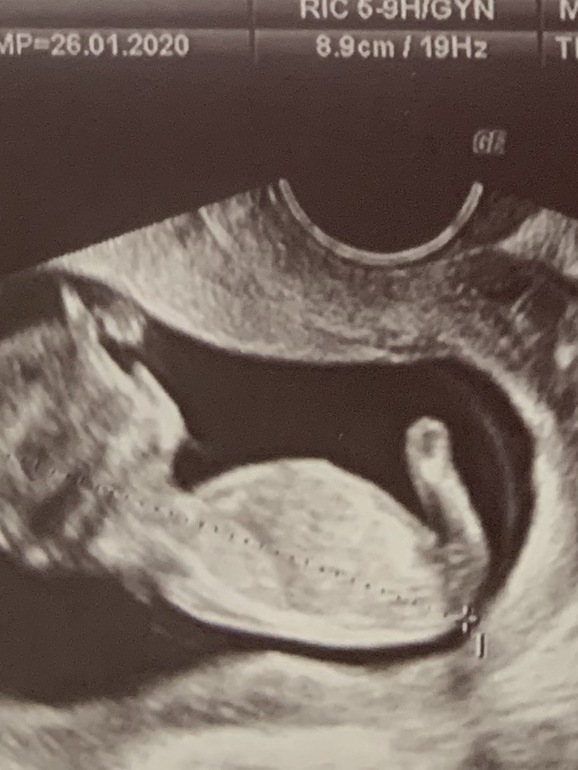

1 скрининг 12+3 ( и вопрос про пол малыша)

Результаты: УЗИ, КТГ, доплера, скрининга5 дней назад ходила на 1 скрининг,посмотрели малышастика какой же он уже человечек,смотрела на него и от счастья текли слёзы ,хотя малыш у меня не первый ,но расплакалась впервые.

По узи все хорошо,сегодня получила результаты крови,риски низкие,единственное риск по возрасту высокий 1:209,мне уже 36,но врач сказала на него не смотри это статистика .

Спросила про пол врач показала отросточек и сказала как у всех на этом сроке или мальчик или девочка,другого не дано,позже узнаём.Но мне кажется девочка будет,прям чувствую что доча! Девочки на последнем фото это отросточек у ножки или нет,не понимаю что , по нему можно пол предугадать?)

В 16 нед узнаете. А то нам парня наобещали в 12 нед. Пусть лучше пока будет тайной. Но я, честно говоря, не вижу ничего у ваших ножек)))